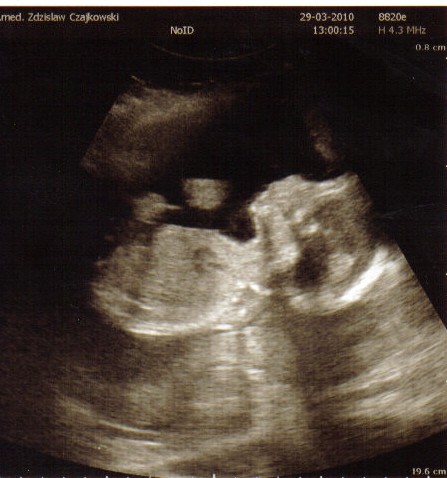

Nie chciała pokazać czyim klonem jest , mamy czy taty

Zobacz załącznik 230489

Zdjęcie do góry nogami , bo i niunia była do góry nogami